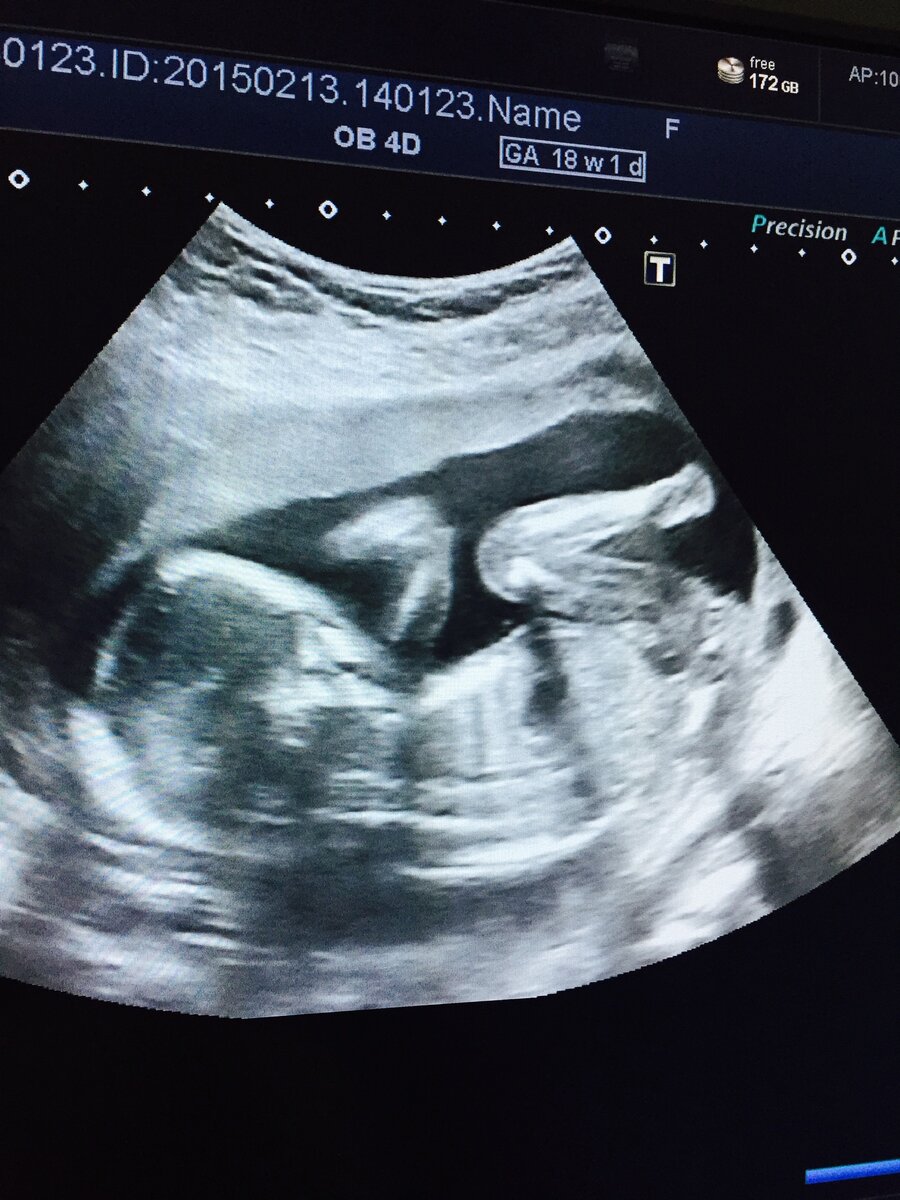

Затем, нужно было сделать скрининг в 18 недель, его я уже сделала в Женской консультации, соответственно бесплатно. Дисплея для родителей в жк нет. И узист был не многословен. Но главное, сказал что все хорошо, и сохранил изображение малыша на экране, предложил мне сделать фото на память)